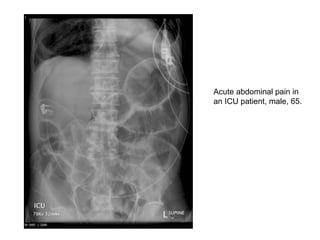

Acute abdominal pain in

an ICU patient, male, 65.

• Rigler’s sign LUQ

• Free

intraperitoneal

gas is widespread

with moderate

dilatation of small

bowel in particular

and there may

also be intramural

gas.